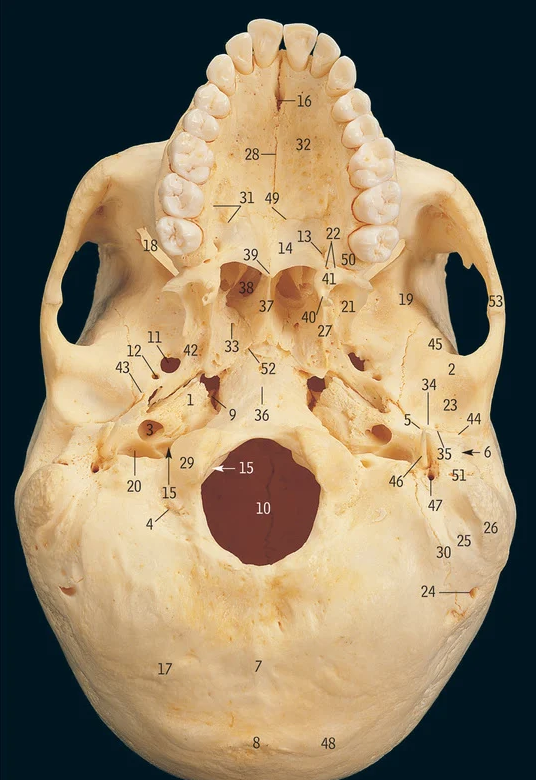

Cribiform plate

6

Crista galli

17

Greater wing of sphenoid bone

32

Lesser wing of sphenoid bone

38

Pituitary fossa

34

Optic canal

42

Superior orbital fissure

12

Foramen ovale

13

Foramen rotundum

14

Foramen spinosum

27

Hypoglossal canal

11

Foramen magnum

Supra-orbital notch

29

Occipital condyle

48

Superior nuchal line

37

Zygomatic process of temporal bone

18

Mastoid processÂ

Petrous part of temporal bone

28

Internal auditory meatus

9

Mandibular fossa

3

Carotid canal

46

Styloid process

47

Stylomastoid foramen